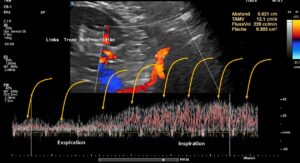

These images show the respiratory variability of volume transport within the tronc réno-rachidèn.